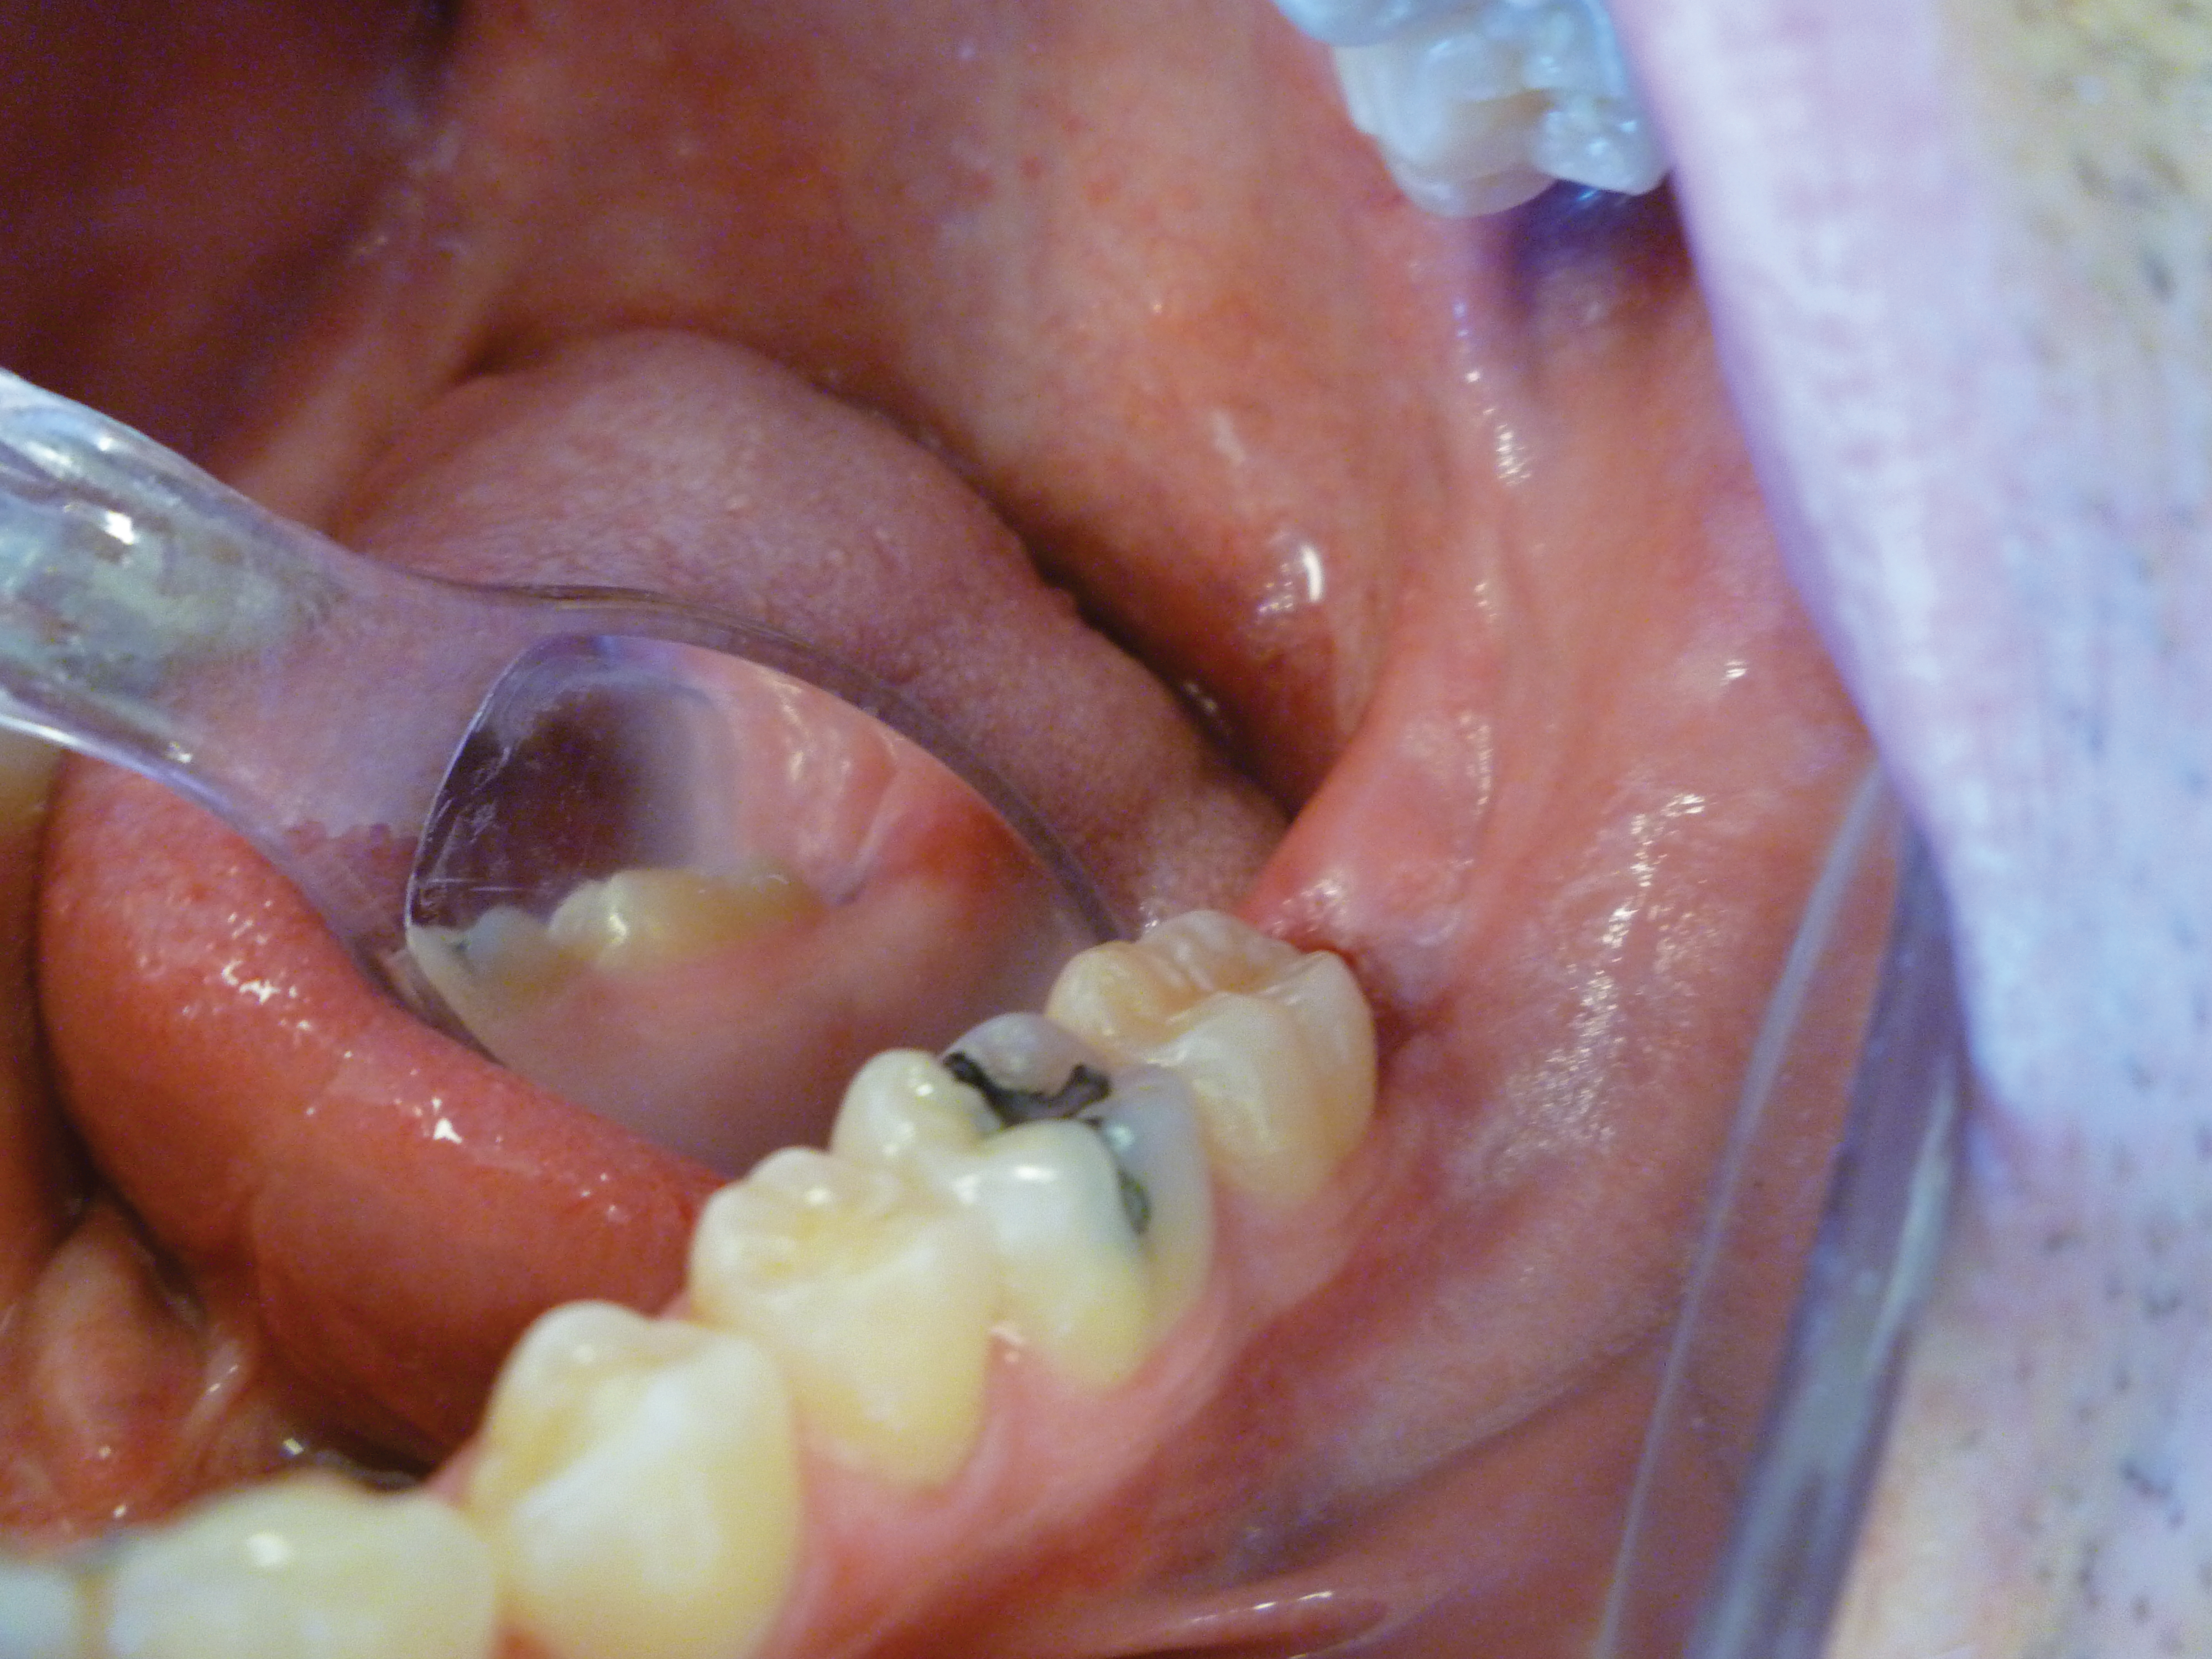

The patient presented with a raised, inflamed, painful operculum distal to the left mandibular second molar (Figure 3). The lesion was red, edematous, and bled easily. A periodontal pocket on the distal of the second molar was >6 mm deep. There was no evidence of abscess.

Fig 3. Preoperative view of the inflamed operculum.

Figure 3

Fig 4. The angled handpiece of the CO2 laser was held perpendicular to the target lesion.

Figure 4